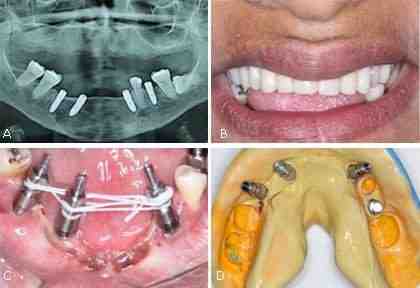

How many implants are needed for full mouth?

Due to the smoother bone of the upper jaw, the minimum number of implants that can be placed for the entire set of teeth is 4 implants, even if the final prosthesis is fixed or removed. You can’t do anything with 2-3 implants in the upper jaw or things will fail.